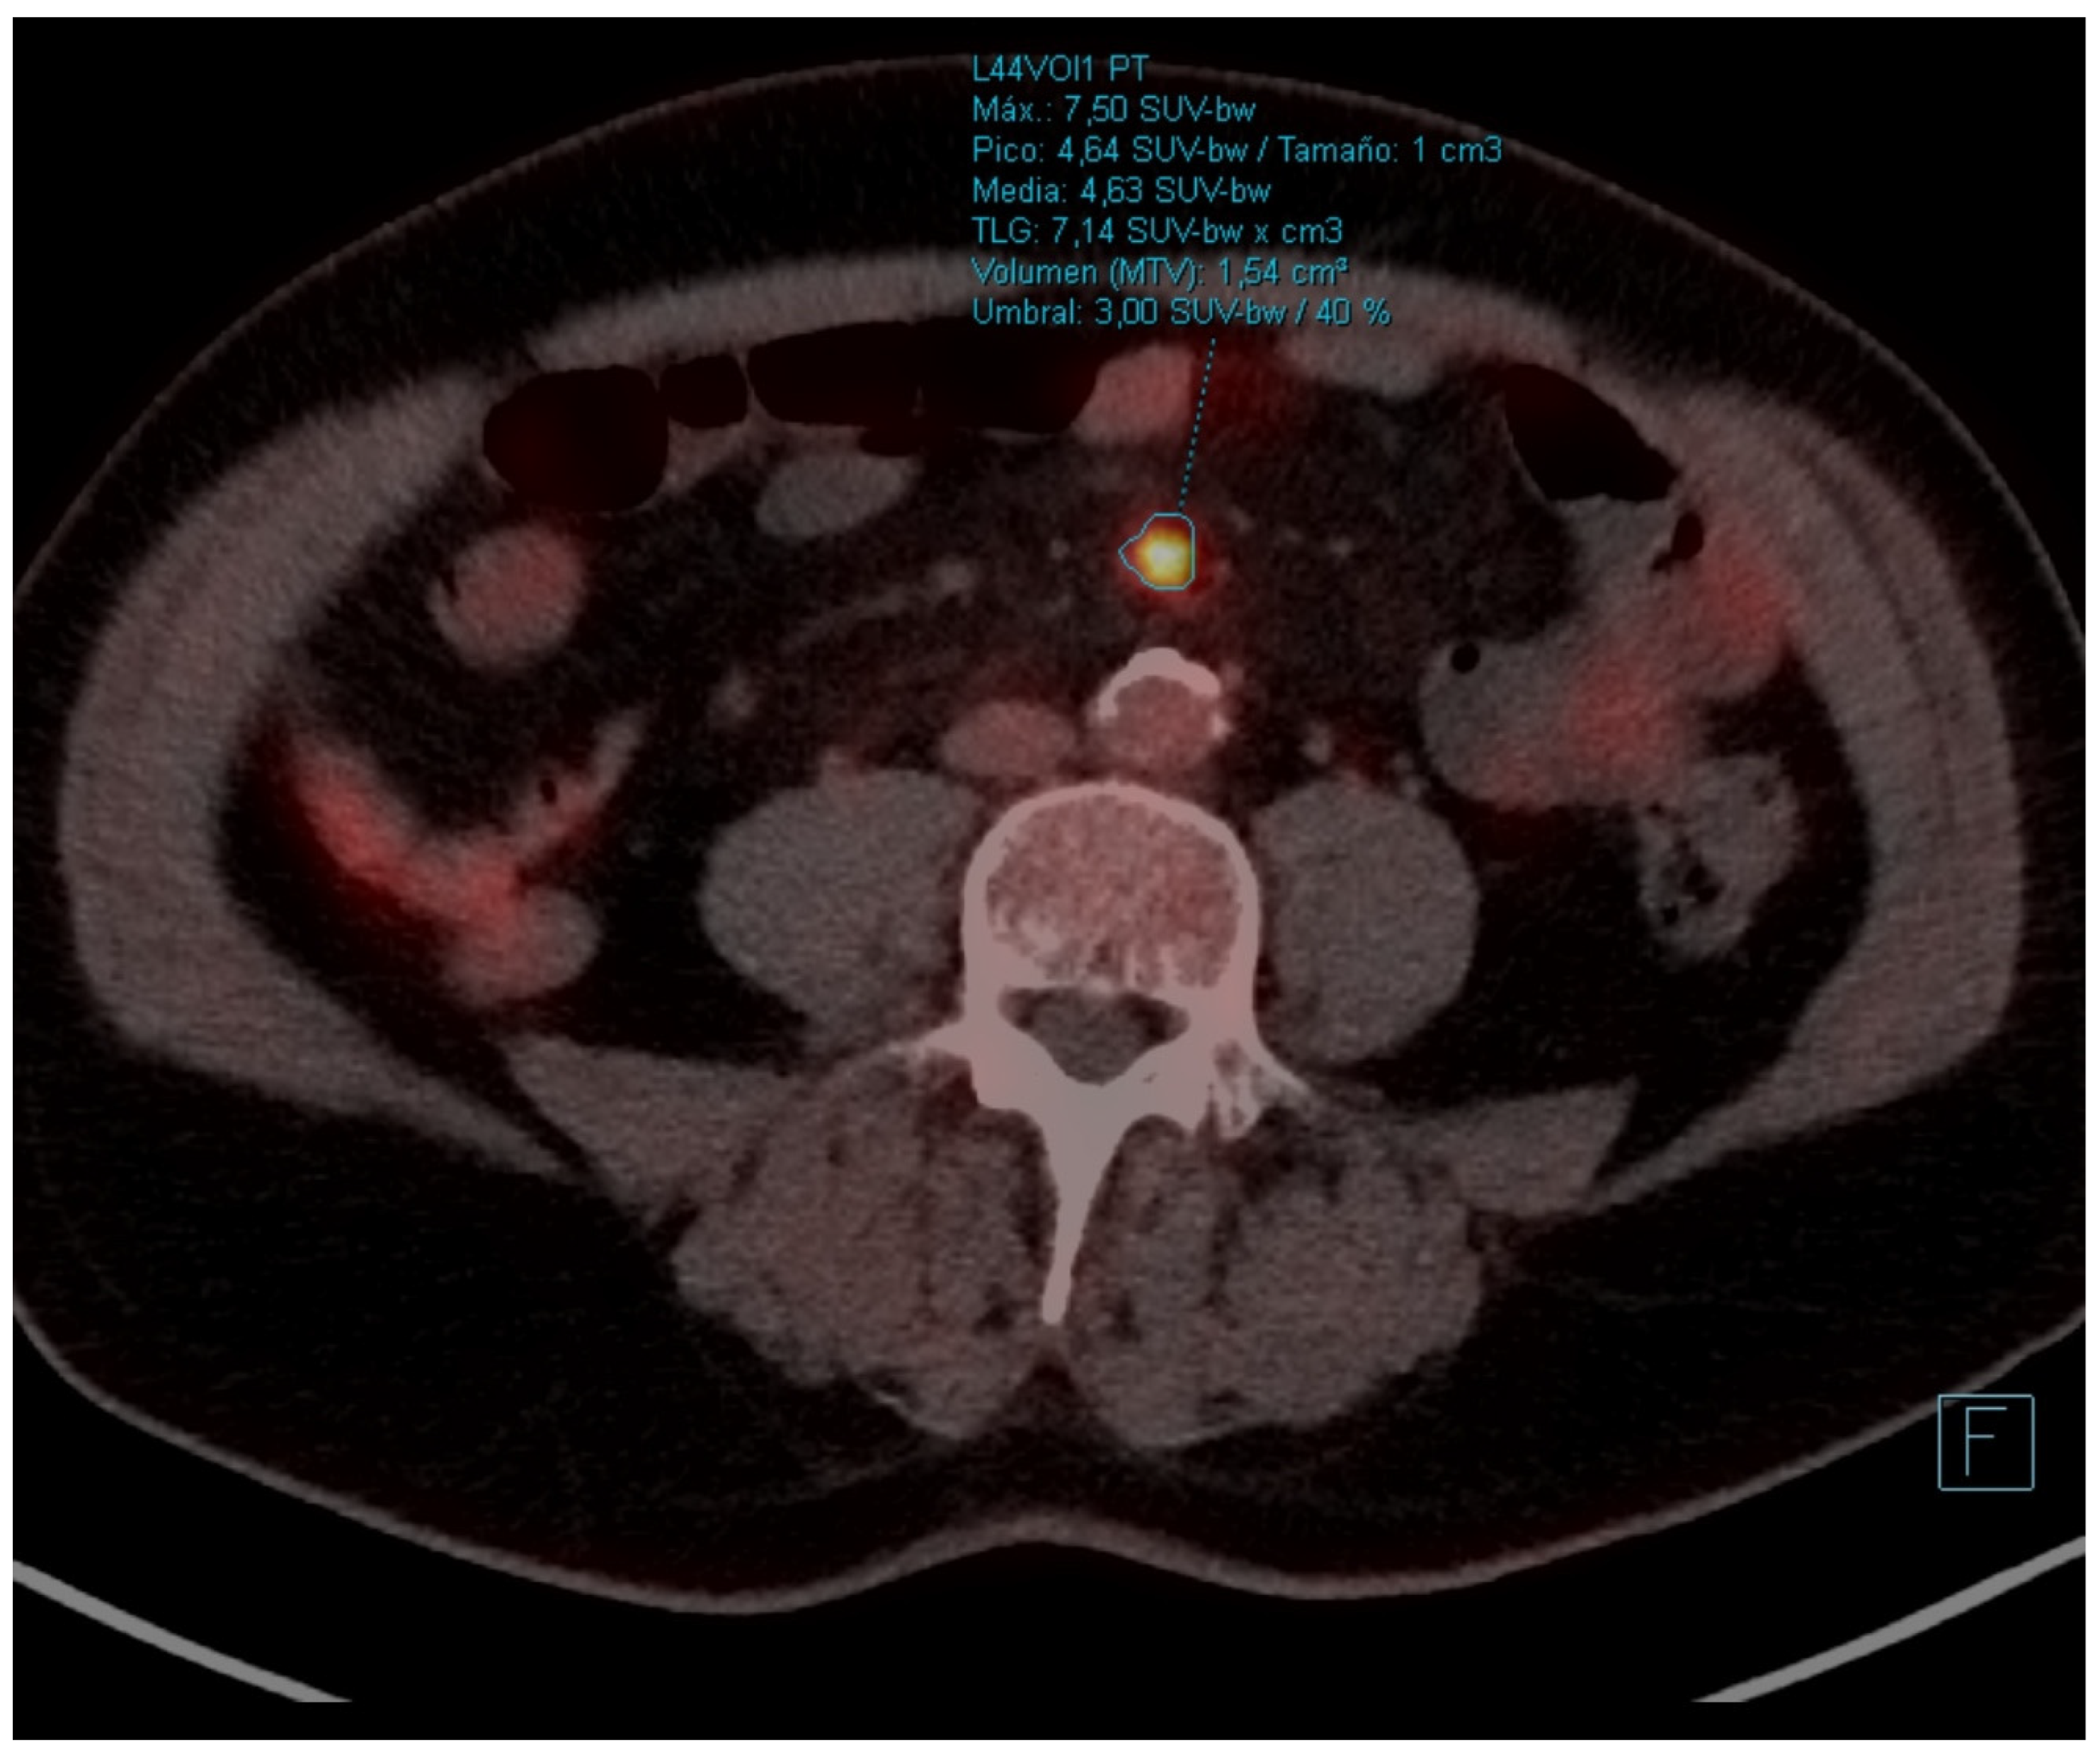

| PET-CT | October 2021 | Re-evaluation | - Hypermetabolic mass (SUVmax 24.72) in left lower lobe of 4.2 × 3.5 cm. - Complete response of the hilar adenopathies, without pathologic uptake. - Focal increase of FDG in pseudonodular formations in mesenteric fat, up to SUVmax 12.48, in relation to mesenteric panniculitis. |

| PET-CT | April 2023 | Severe abdominal pain that had consulted 4 times in the emergency room | - Hypermetabolic persistence of adenopathies in the right cervical chain, lower paratracheal and right pulmonary hilum with dissociated response, some have progressed and others have improved. - Signs of mesenteric panniculitis, visualizing increased pseudonodular formations, several with FDG uptake up to SUVmax 7.50, not present in the previous study. |